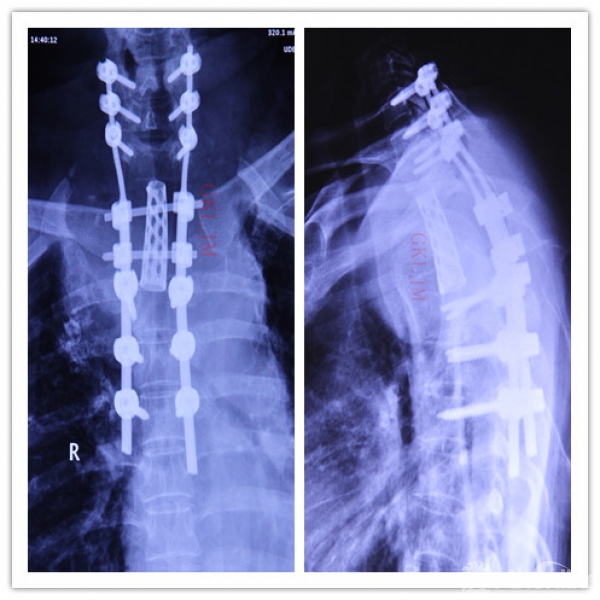

术后X线正侧位平片